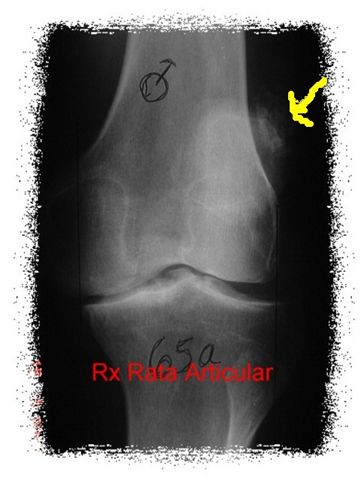

RATA ARTICULAR